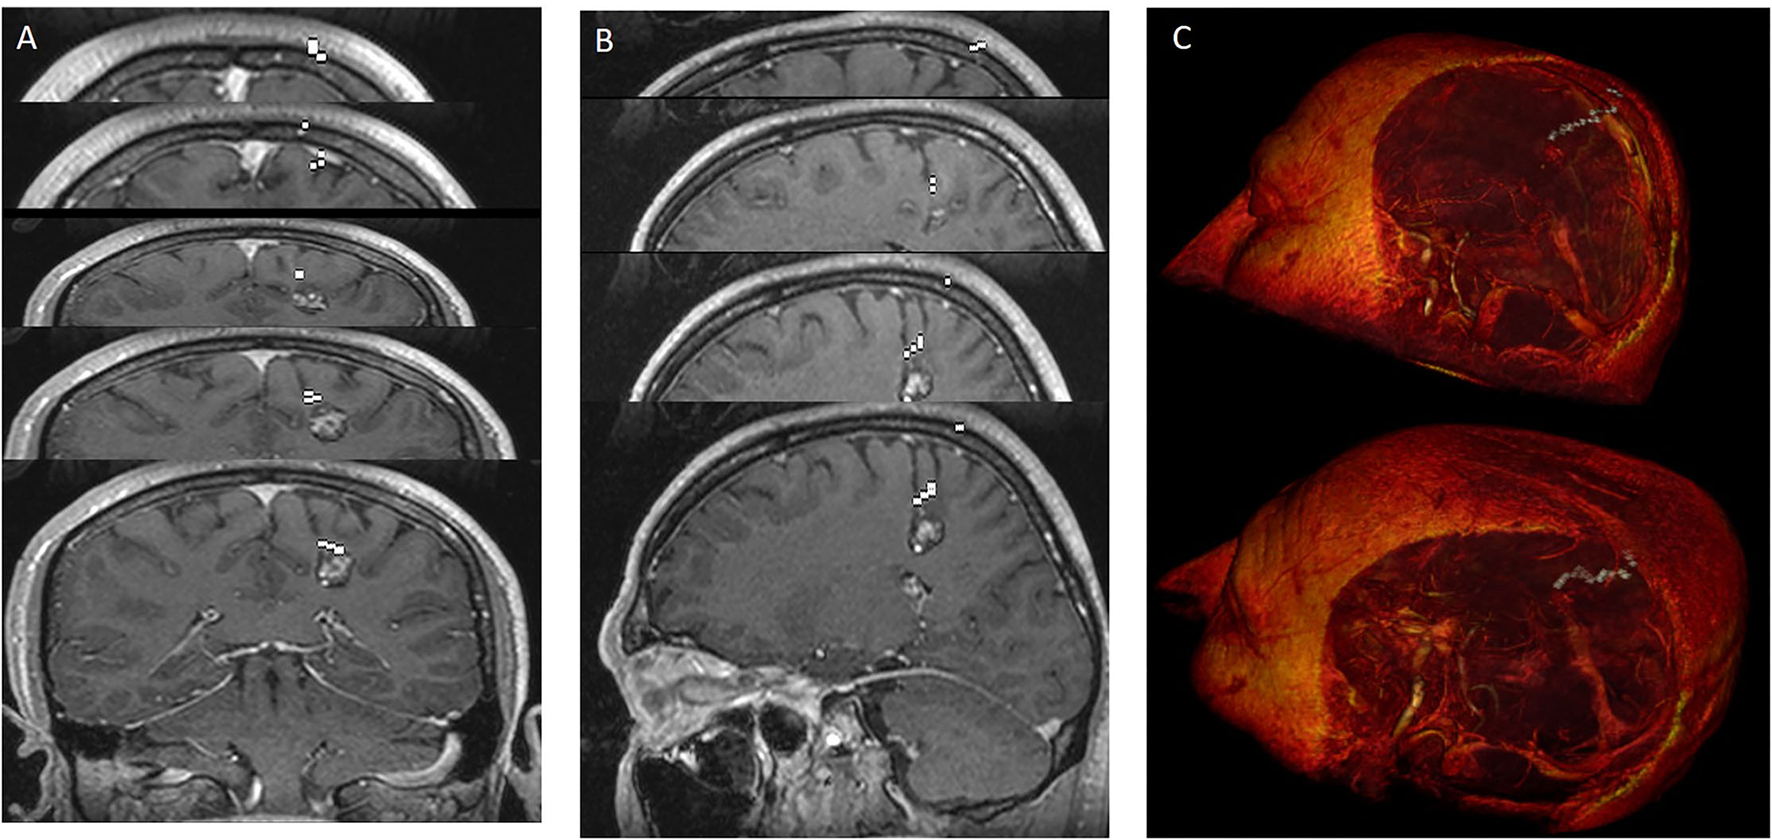

The borders of the preoperative brain tumor lesion (reward) were determined as the contrast-enhancing area in T1 contrast MRI imaging (19). Tracts with diffusion tensor imaging (DTI), arterial anatomy with contrast-enhanced MRI angiography (CE-MRA), and those with tumor tissue (20) superficial cortical vessels and dural sinuses are used in surgical planning with MRI venography (21) (Figure 2). DICOM images in the respective sequences were imported into the labeling program (labelme 4.6.0, https://github.com/wkentaro/labelme). Functional anatomical areas were marked and labeled by the radiology and neurosurgeon specialist (Figure 3). The pixel and voxel values of the anatomical point and the anatomical structure of the point were listed by labeling (22, 23). This gave us the advantage of trading in a cubic system with matrixes.

Figure 3. Labeling using contrast-enhanced T1 axial image of cranial MRI. (A) Superior sagittal sinus marked in red at the vertex's midline. (B) Superior sagittal sinus marked with red in the midline in the supraventricular area, precentral gyrus marked with green, postcentral gyrus marked with turquoise, superficial cortical veins marked with pink on the left and dark yellow on the right adjacent to the bilateral frontal lobes. (C) Right basal ganglia and thalamus marked with yellow in the right cerebral hemisphere at the ventricular level; left basal ganglia and thalamus marked with light red in the left cerebral hemisphere at the ventricular level, Broca's area in the left frontal lobe with light yellow, Wernicke's area posterior to Sylvian fissure marked with orange; The anterior cerebral arteries are marked in light green anteriorly in the midline, the corpus callosum splenium in green and the sinus rectus in blue in the midline posteriorly. (D) Right postcentral gyrus marked red, cavernom/tumor marked yellow-green, pericallosal artery marked blue on the midline and posterior inferior frontal artery marked blue.

We used (512 × 512 × 144) axial T1-weighted MRI images of one patient with a brain tumor in DICOM format as a case study. We utilized 16 × 16, 32 × 32, 40 × 40, and 64 × 64 path dimensions to evaluate the success of the proposed system architecture. In the first stage, 20 optimal linear paths were extracted for each dimension by using the new heuristic-based algorithm. The optimal nonlinear path was extracted by using the starting points found in the 16 × 16 path dimension. For the 16 × 16 path dimension, the proposed heuristic found 745,984 possible entry points. The areas in Table 2 and the target tumor tissue were accepted as reference points. This algorithm gave input fields of desired diameter and size. These 745,984 linear paths were compared according to the reward and penalty points. By using the intermediate steps, the 20-optimal linear paths were chosen. Then the starting points of these paths were used as reference entry points of the Q-learning algorithm (Figure 4) in the second stage. Then, a matrix size of 78,030 × 78,030 was created and worked on 50 × 25 × 78,030 points for Q-learning. Extracranial areas were excluded. It was enough to find 500,000 epoch paths in a 16 × 16 × 35 environment, and it almost took 70 min. The Q-learning algorithm returns as the best way “node” (Figure 5). Then, the positions of these node values in the matrix were found and the x, y, and z coordinate values were reached. Thus, the coordinates representing the best path were extracted from the DICOM images. The most ideal transcortical tumoral pathway was revealed in Figure 6.

Figure 5. The most ideal cortico-tumoral approach is recommended by RL. Images were added one after another to show the nonlinear pathway. RL extracted the most optimal pathway by performing a random-onset point analysis of the entire intracranial area. Demonstration of the approach reaching the tumor from the base of the postcentral sulcus. (A) howing the pathway in coronal sections. (B) Showing the pathway in sagittal sections. (C) Showing the 3-dimensional pathway with image processing.